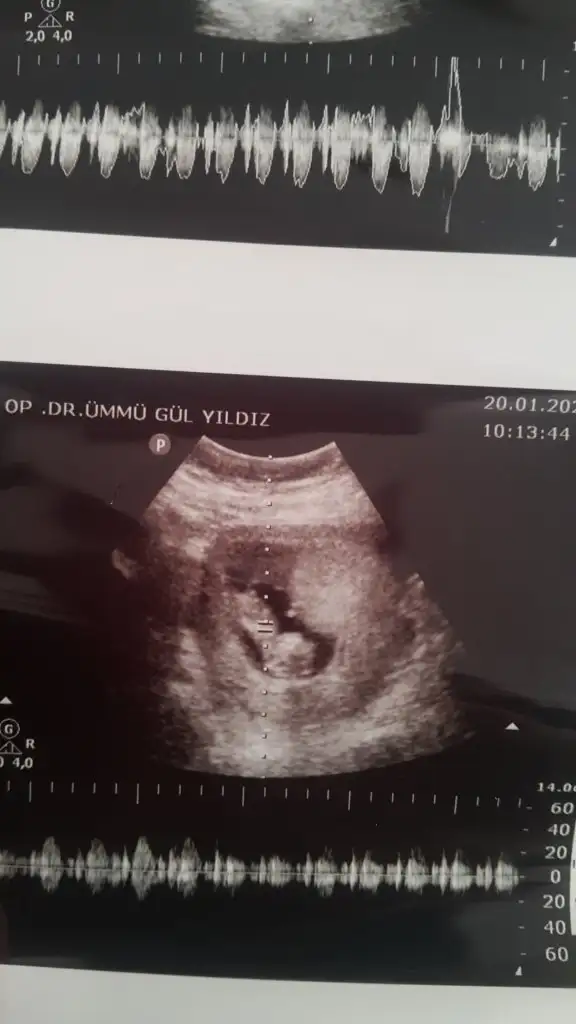

dr soylemeden siz gorun genital nub teorisi ( bebegin cinsiyeti)

mrhaba lütfen yorumlarmisiniz sizce kızmı erkekmi bi arkadas icin soruyorum

Sevgili İkra,

Yorumlarsan çok sevinirim. ☺️❤️